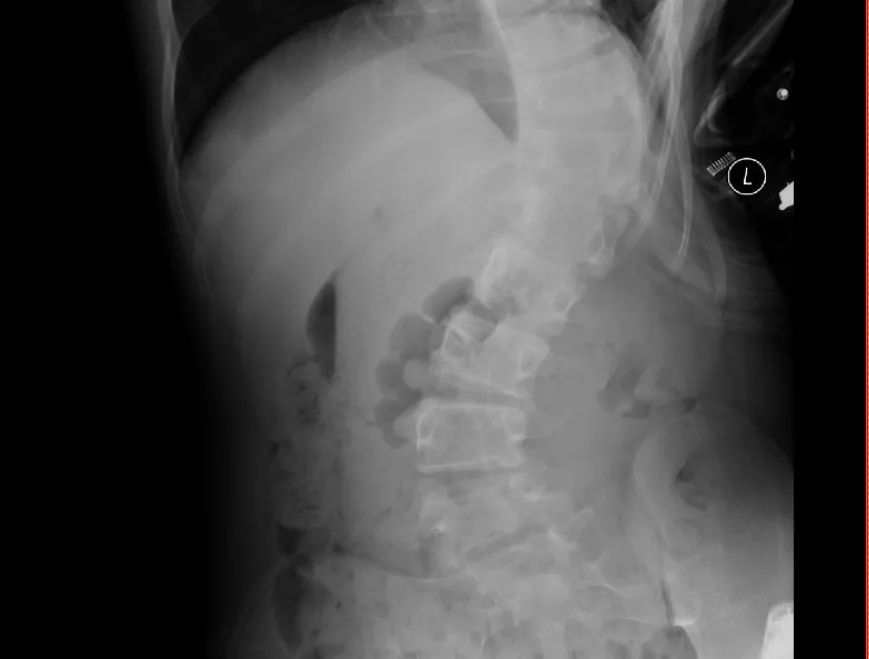

入院骨外科三区(脊髓脊柱外科)后,立即给予完善相关检查,检查结果排除了先天性骨结构异常、脊髓神经等疾病所致脊柱侧弯。结果提示小明患的是:特发性脊柱侧弯!

特发性脊柱侧弯(idiopathic scoliosis)是指一种脊柱畸形,儿童或青少年期间脊柱侧弯达到10度以上即可确立诊断。该疾病常常在儿童或青少年时期发病,如果不及时治疗,会导致脊柱扭曲,造成身体不平衡和心理困扰。

为了给予小明及时,最优、个性化的治疗,骨外科三区(脊髓脊柱外科)专家团队结合检查结果对小明的病情进行详细的分析和讨论,明确手术方式和手术部位,并与团队提前做好各项术前准备,最终确定为特发性脊柱侧弯矫正手术,手术由仇继任主任医师、罗坤烈副主任医师等专家为小明开展。术中,经过精密计算,成功将小明的脊柱进行了矫正,使其身体恢复了平衡,术后2天,小明已经可以在胸腰椎支具固定下进行下床活动并逐步进行功能锻炼。术后测量,小明的身高也从原来的158cm增高至164cm,患者及其家属对手术效果非常满意。目前,患者恢复良好,已经顺利出院,出院时身体平衡稳定。